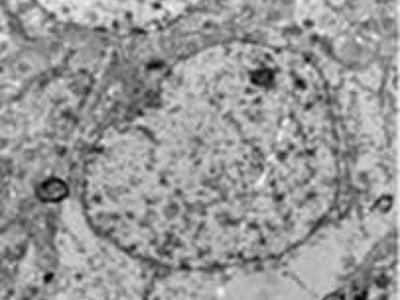

中药单体丁基苯酞可治疗弥漫性脑损伤

注射dl-3n丁基苯酞后,弥漫性脑损伤大鼠的大脑皮质神经细胞损伤明显减轻,核仁清...